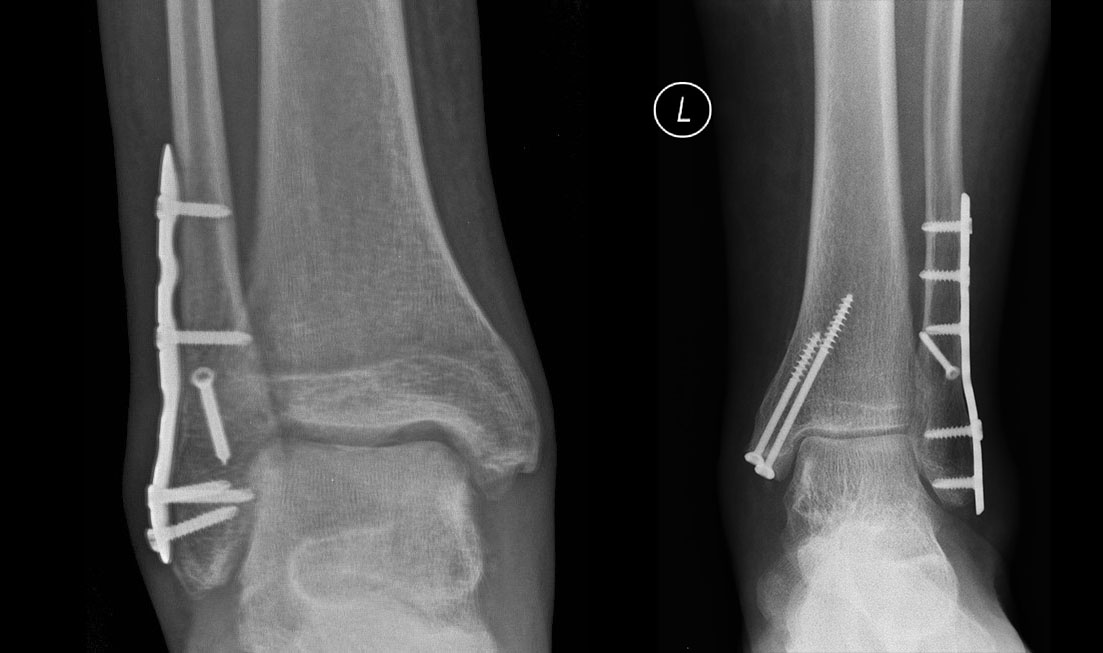

Złamanie kostek goleni (operacje z użyciem nowoczesnych tytanowych implantów)

Złamanie kostek goleni to dość powszechny uraz, a w zasadzie pełne spektrum urazów od najłagodniejszego złamania pojedynczej kostki (przyśrodkowej lub bocznej) aż do skomplikowanych urazów trójkostkowych z uszkodzeniem więzozrostu piszczelowo-strzałkowego włącznie. Znaczna większość złamań kostek goleni w dzisiejszych czasach wymaga leczenia operacyjnego. Tylko taki sposób postępowania daje najlepsze rezultaty i pozwala na przywrócenie optymalnej funkcji stawu skokowego. Zastosowanie płytek, wkrętów i innych specjalnych implantów najnowszej generacji, łącznie z odpowiednią techniką operacyjną i doświadczeniem w leczeniu tych urazów, pozwala do minimum skrócić okres unieruchomienia oraz przyspieszyć i zintensyfikować rehabilitację pooperacyjną. W leczeniu złamania kostek goleni, a przez to możliwej do uzyskania funkcji kończyny, kluczową rolę odgrywa jak najdokładniejsze odtworzenie powierzchni stawowej stawu skokowego i jak najszybsze podjęcie fachowej intensywnej rehabilitacji.